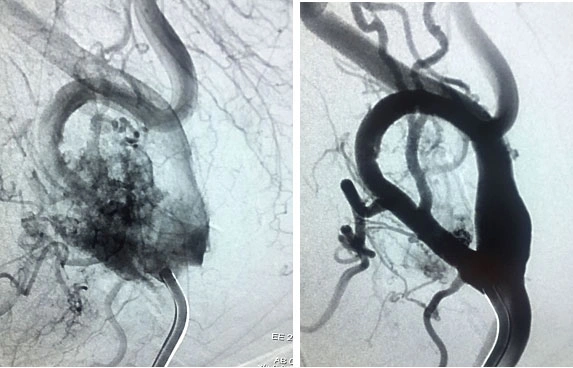

2. Embolizzazione

Una volta completata l’arteriografia e confermata la possibilità di intervento chirurgico, nella maggior parte dei casi si procede con l’embolizzazione. Questo trattamento consiste nel bloccare i vasi che alimentano il tumore, mediante il posizionamento di piccole particelle o spirali metalliche all’interno di questi vasi. L’obiettivo dell’embolizzazione è ridurre la vascolarizzazione del tumore, rendendo l’intervento chirurgico più sicuro e meno rischioso.

Per garantire il massimo dell’efficacia, l’embolizzazione dovrebbe essere effettuata entro 72 ore prima dell’intervento chirurgico, e richiede un ricovero ospedaliero per monitorare il paziente.

Procedura di embolizzazione per ridurre la vascolarizzazione di un tumore del glomo carotideo.